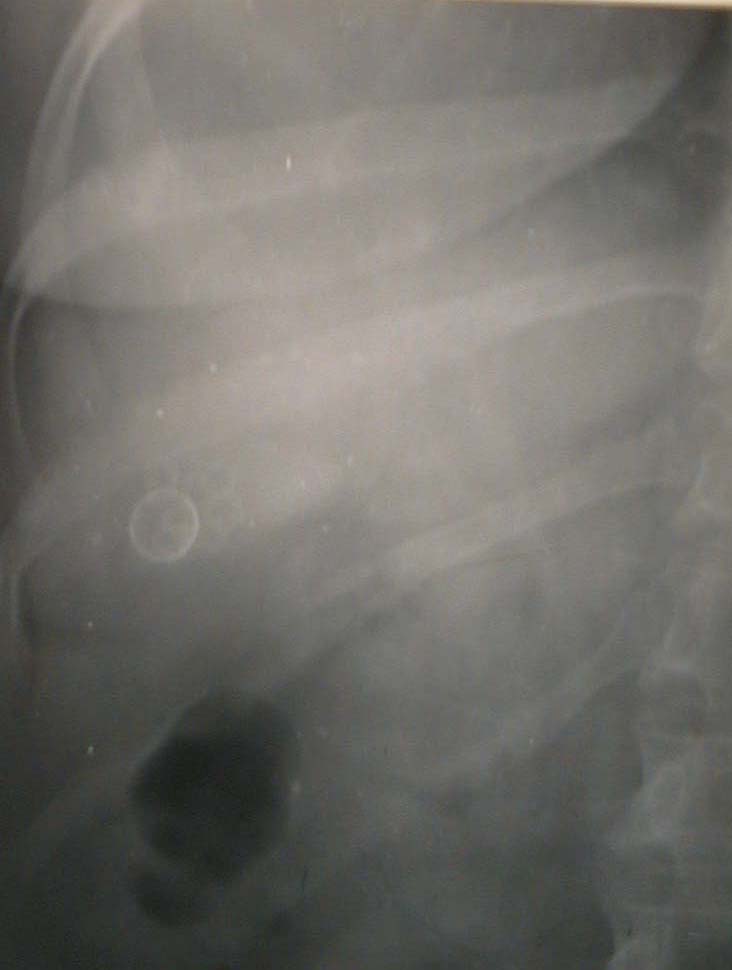

Gallbladder Lithiasis

(M.F., m., 45 ani / years old)

Clinical Manifestations: upper abdomen pain, nausea.

I.V. Cholecystocholangiography: radiolucent image with radioopaque halo in the right upper quadrant.

Operation:  subserosal direct cholecystectomy.

Surgical Specimen: thick-walled gallbladder, containg one 1cm diameter oval calculus and six 0,3cm diameter round calculi.